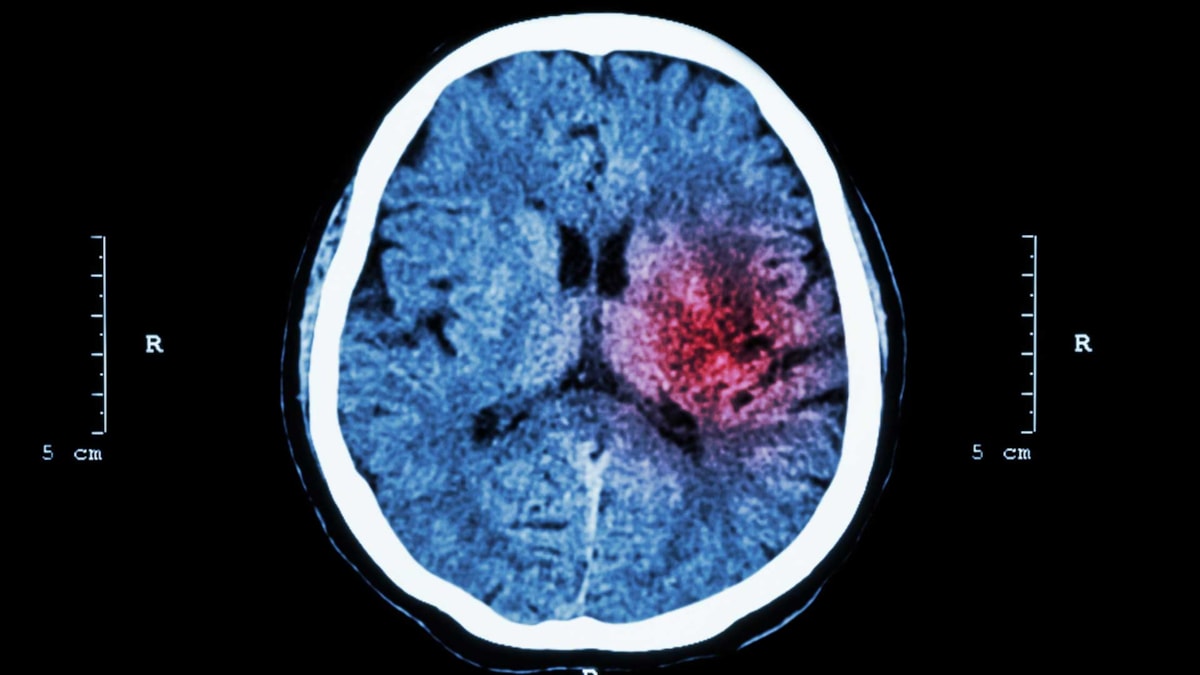

For å behandle hjerneslaget må en skille mellom hjerneinfarkt og hjerneblødning. Da må det tas CT- eller MR-bilde av hodet. Vanligst er det å ta et CT-bilde først. Dette gjøres raskt etter innleggelse i sykehus. En blodpropp ses ikke alltid på de første bildene, mens en blødning ses ofte umiddelbart.